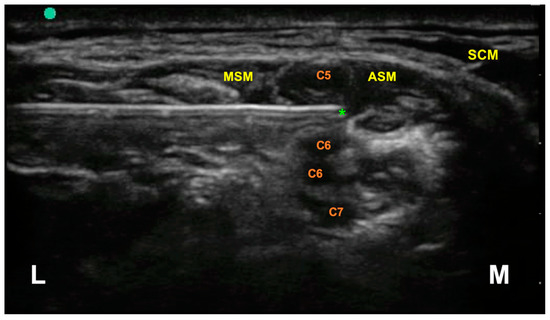

2. Methods